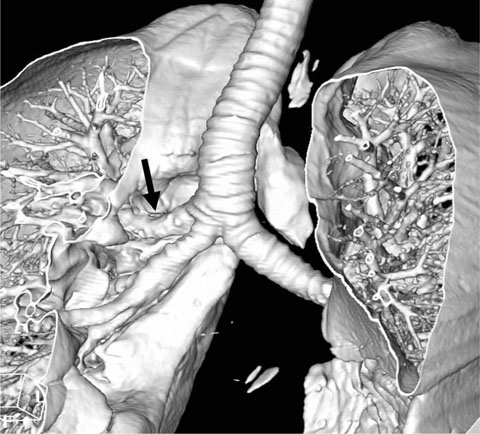

Tracheobronchial Branching Anomalies

- There are various congenital anomalies with respect to the number, length, diameter, and location of tracheobronchial branching patterns. The tracheobronchial anomalies are classified into two groups. The first one, anomalies of division, includes tracheal bronchus, cardiac bronchus, tracheal diverticulum, pulmonary isomerism, and minor variations. The second one, dysmorphic lung, includes lung agenesis-hypoplasia complex and lobar agenesis-aplasia complex.